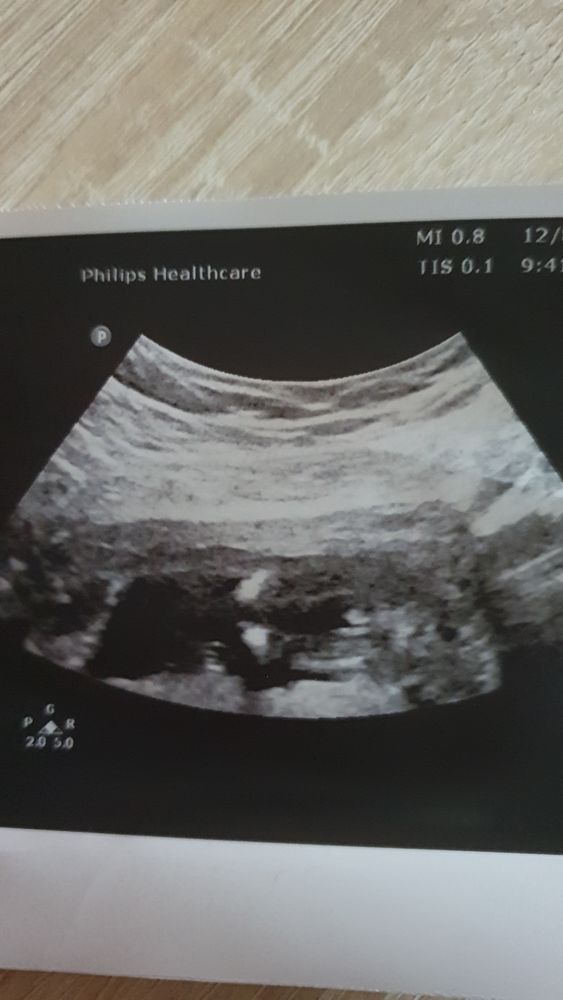

Кто в теремочке живёт?

Похоже на мальчишечку…💙

Как тут вообще хоть что-то увидеть ??? Где тут вообще человек ? 😂😂😂😭😭😭

Карина, это ноги и промежность. Так сказать вид снизу😅

Саламандра, ааа , теперь вижу)

Это торчит половой бугорок. Боком смотреть нужно ) с попы сейчас не определить )

Похоже, что брат.

Похоже на мальчика)

Вроде пацан!)) Но я не разбираюсь)))

Вообще я бы сказала мальчик, но посмотрела ваш срок и вроде рановато для такого ракурса. Обычно сбоку по наклону полового бугорка смотрят в первом триместре.

У НАС БУДЕТ ДОЧЕНЬКА💗🙏🏻😭🥰 Узнала пол !!! У меня лёгкий шок )))